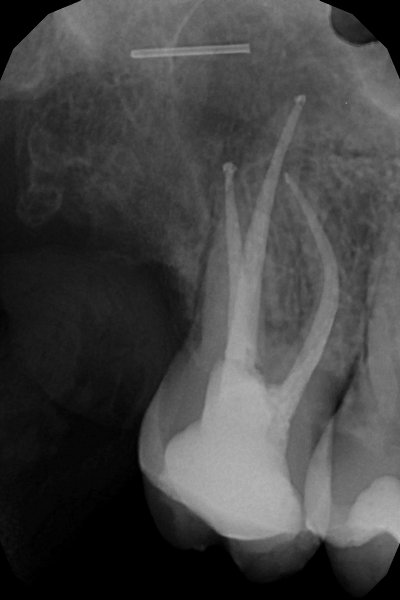

Radiografía de un diente endodonciado. Clínica Dental Fernández León